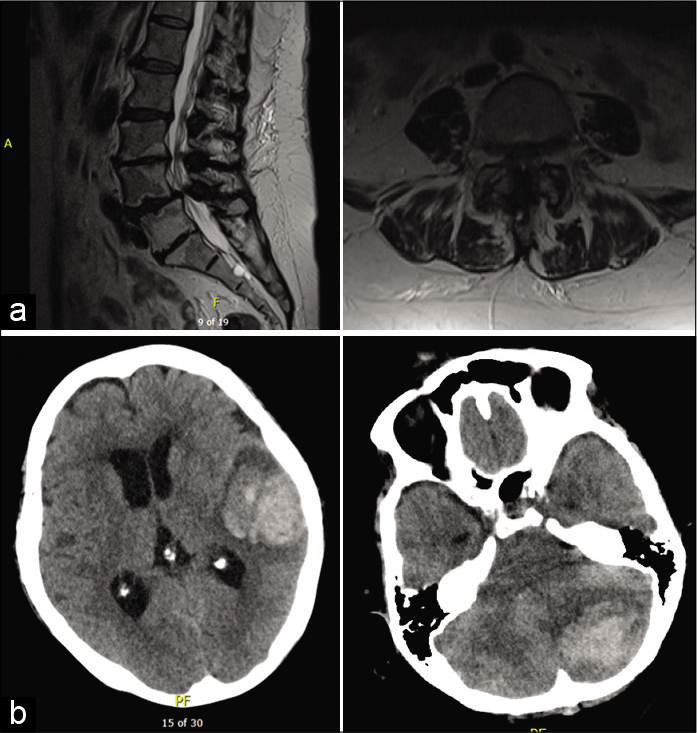

Unraveling a rare cause of spinal stenosis: Coexistent AL and ATTR amyloidosis involving the ligamentum flavum